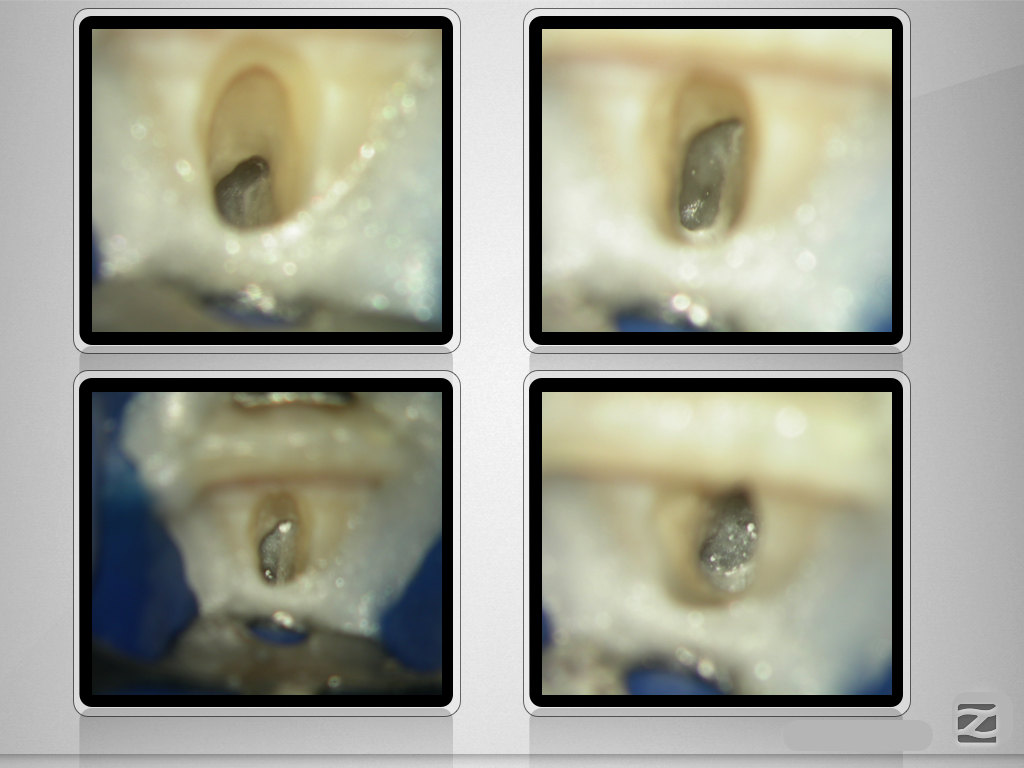

Folgen eines Milchzahntraumas (3)